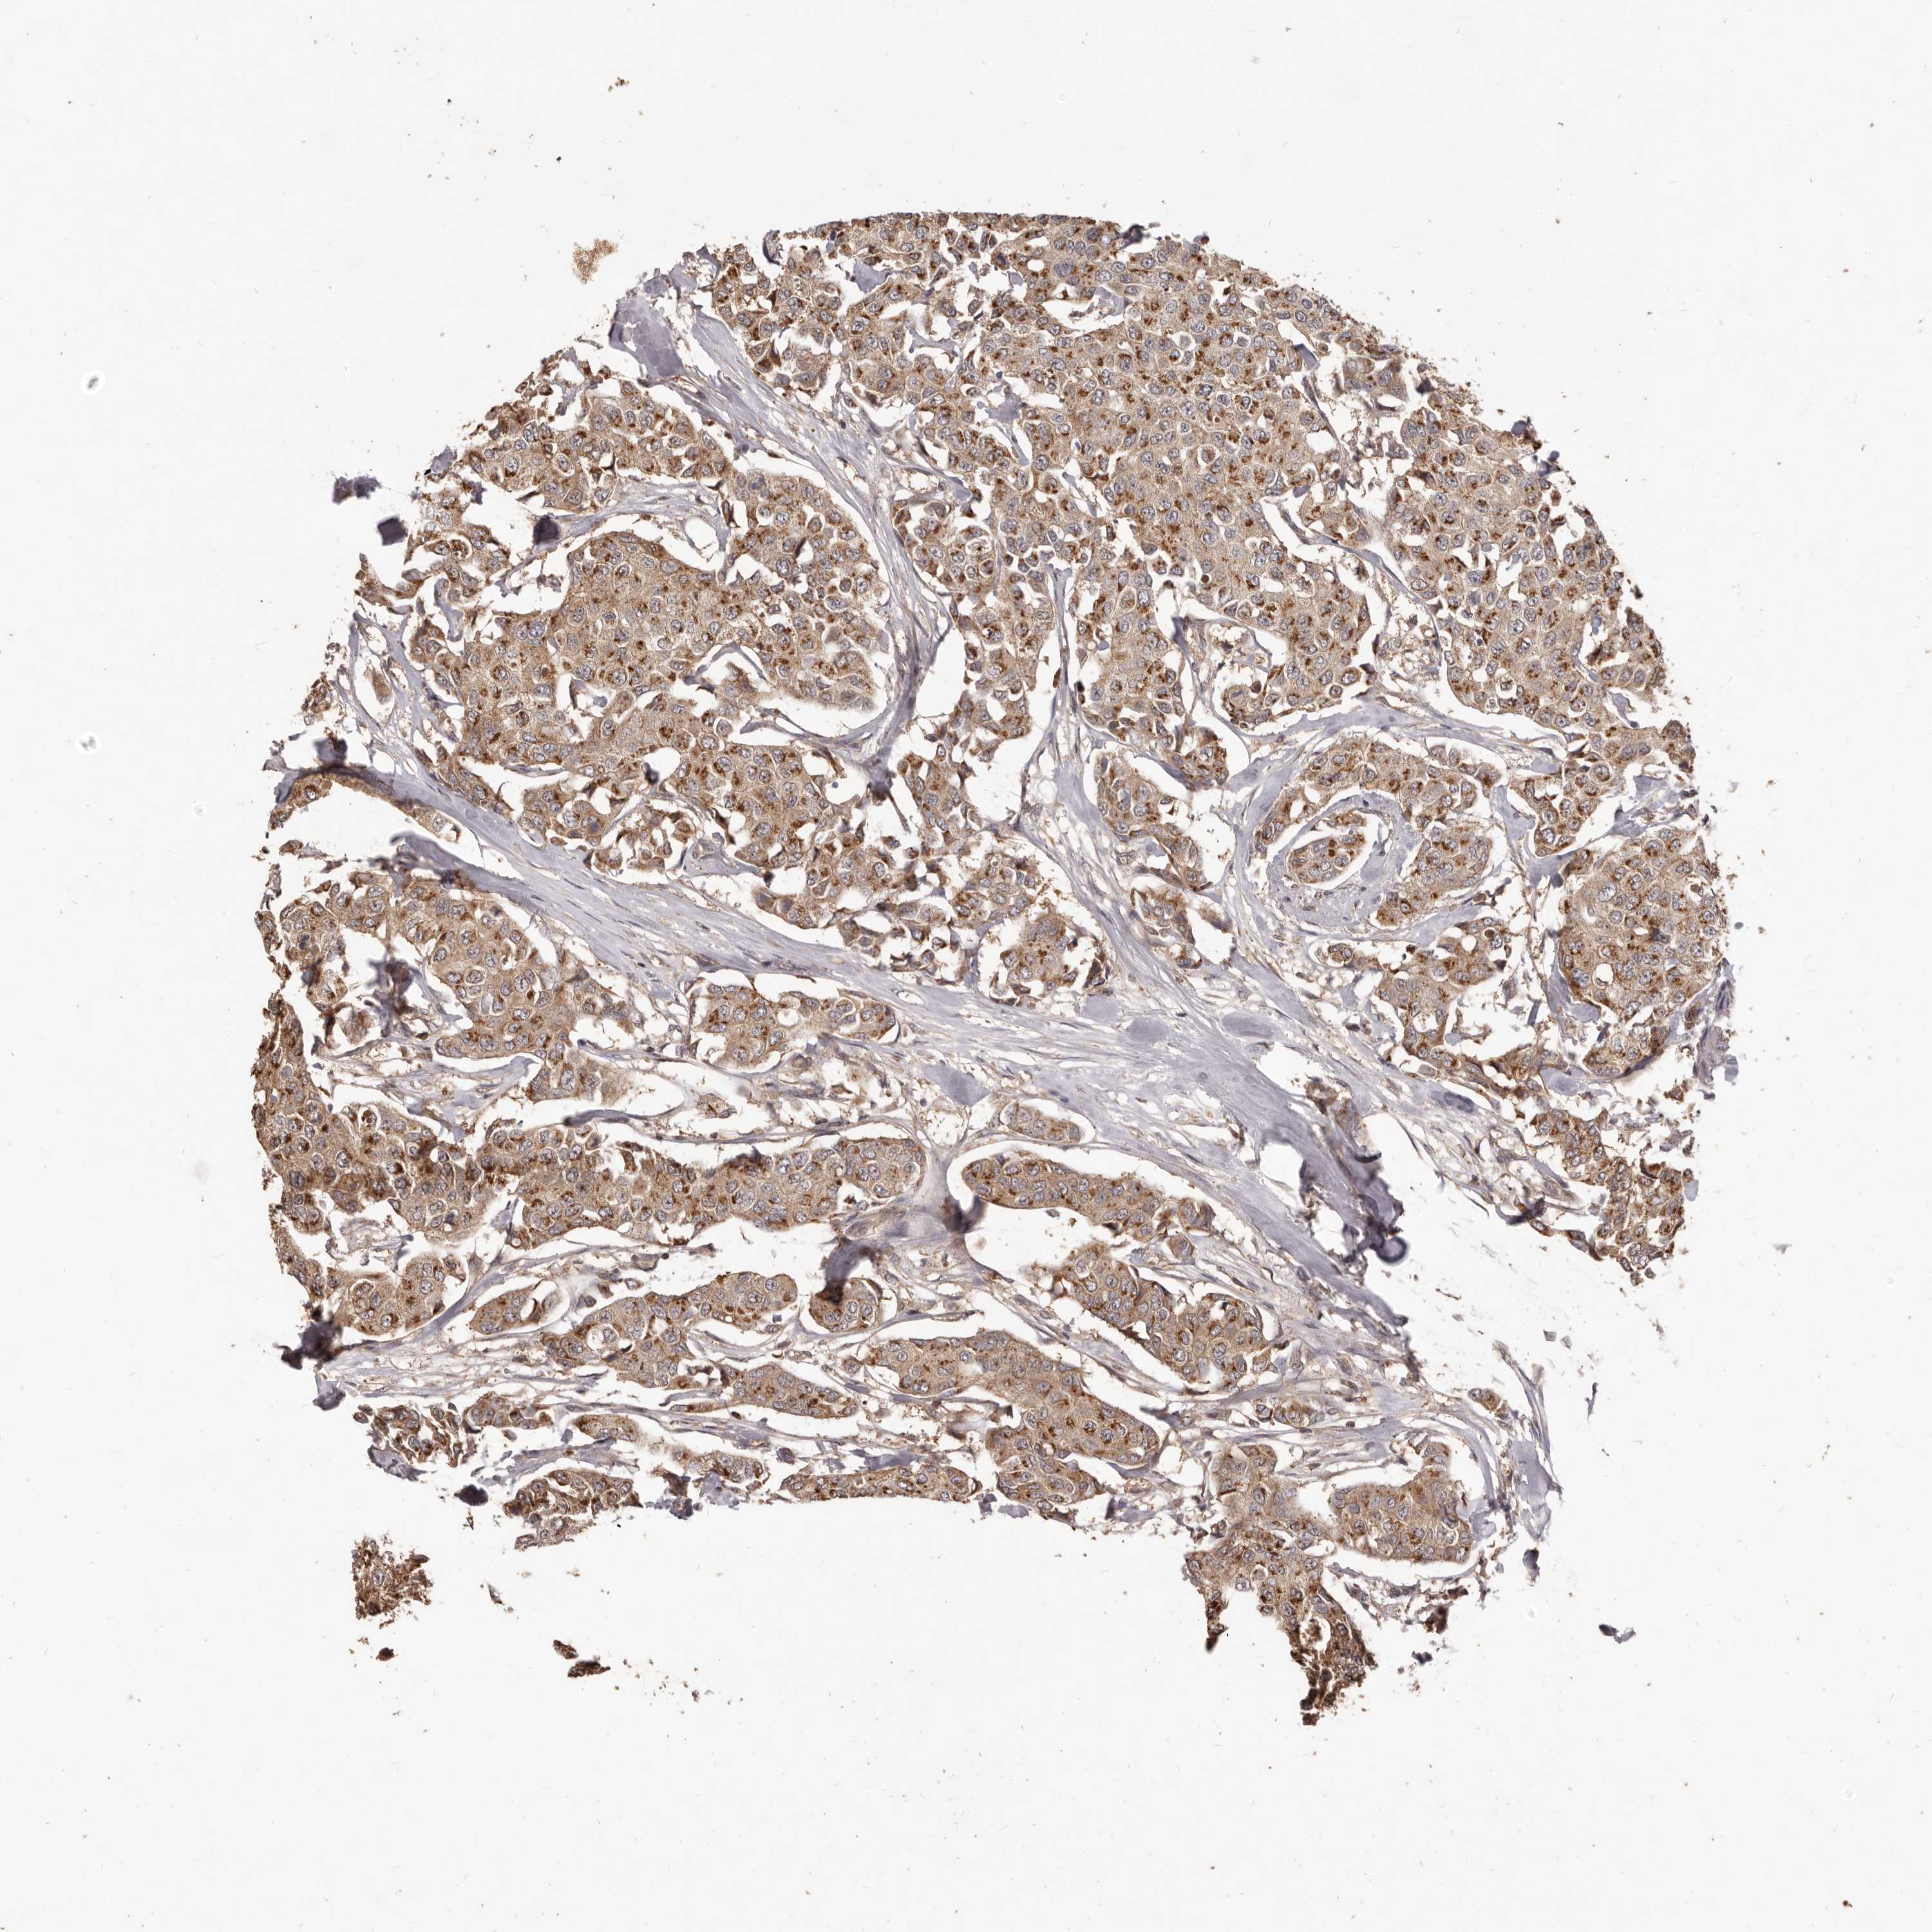

CANCER BREAST CANCER Show tissue menu

BRCA TCGA BRCA VALIDATION PROTEIN EXPRESSION